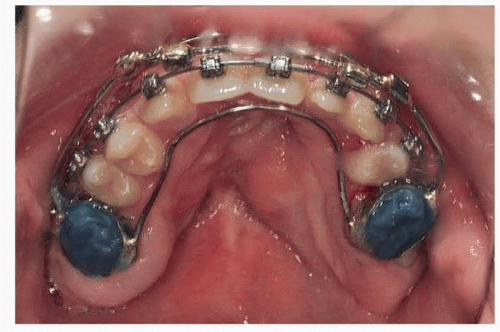

The dental impressions are sent to a dental lab for creation of a custom-made intraoral splint.

The splint acts as the link between the Le Fort I segment and the distraction device and is applied a few days before the surgical procedure.

The splint is then cemented to the first permanent or second primary maxillary molar (FIG 3).